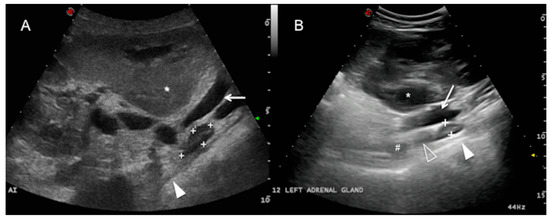

The left adrenal gland was only visualized in 7 of the 25 cows examined in this study, ventral to the abdominal aorta and the caudal vena cava from the right side. It was more clearly detected in a longitudinal plane from the flank (3/7) and the 12th ICS (3/7), and it was only visible at the level of the 11th ICS in one cow, caudomedial to the right kidney and caudal to the main arterial aortic branches of the abdomen (coeliac and cranial mesenteric artery) (Figure 3). The left adrenal gland was elongated along the longitudinal plane, sometimes bilobed, and of mean length 3.72 ± 0.95 cm (range 1.86–5.58) and mean thickness 1.36 ± 0.33 cm (range 0.71–2.01). It was not identified in any of the cows from the left abdominal transcutaneous approach. The adrenal cortex and medulla were only discernible in 3 of the 7 cows in which the left adrenal gland was visualized. Adjacent to the gland, a hyperechoic line with acoustic shadowing indicates the presence of the dorsal sac of the rumen. The ruminal wall layers were sometimes identified as a combination of hypo and hyperechoic lines [1] (white solid arrowhead, Figure 3). The main hindrance to identifying the left adrenal gland was interference from the gas in the gastrointestinal tract adjacent to the dorsum of the abdominal cavity (mainly in the rumen and large intestine).

Figure 3. Left adrenal gland. Dorsal plane from the right paralumbar abdomen (A) and 12th intercostal space (ICS) (B) of two different cows, showing the left adrenal gland (between cursors or “+” sign) adjacent to the aorta (not visible in this plane) and the caudal vena cava (white arrow), medial to the right kidney (asterisk). Note that the gland is in close contact with the dorsal sac of the rumen (white solid arrowhead) and caudal to the coeliac artery (#) and the cranial mesenteric artery (white hollow arrowhead). The adrenal cortex and medulla can be differentiated. Cranial is to the left of the image. AI = left adrenal gland.